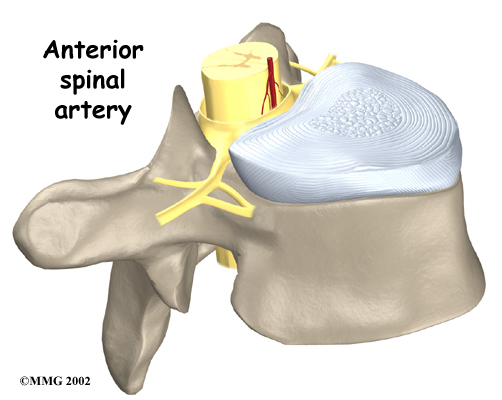

The spinal canal is a hollow tube inside the spinal column. It surrounds the spinal cord as it passes through the spine. The spinal cord is similar to a long wire made up of millions of nerve fibers. Just as the skull protects the brain, the bones of the spinal column protect the spinal cord. The spinal canal is narrow in the thoracic spine. Any condition that takes up extra space inside this canal can injure the spinal cord.

Blood vessels that run up and down the spine nourish the spinal cord. However, only one vessel, the , goes to the front of the spinal cord in the area between T4 and T9. Doctors call this section of the spine the critical zone. If this single vessel is damaged, as can happen with pressure from a herniated thoracic disc, the spinal cord has no other way to get blood. Left untreated, this section of the spinal cord dies, which can lead to severe problems of weakness or paralysis below the waist.

The spinal cord may be injured when a thoracic disc herniates. The spinal canal of the thoracic spine is narrow, so the spinal cord is immediately in danger from anything that takes up space inside the canal. Most disc herniations in the thoracic spine squeeze straight back, rather than deflecting off to either side. As a result, the disc material is often pushed directly toward the spinal cord. A herniated disc can cut off the blood supply to the spinal cord. Discs that herniate into the critical zone of the thoracic spine (T4 to T9) can shut off blood from the one and only blood vessel going to the front of the spinal cord in this section of the spine. This can cause the nerve tissues in the spinal cord to die, leading to severe problems of weakness or paralysis in the legs.